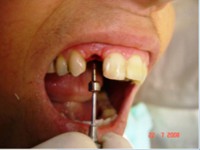

Carga Imediata após exodontia atraumática

- Implante imediato

- Carga imediata

- Coroa protética cerâmica imediata